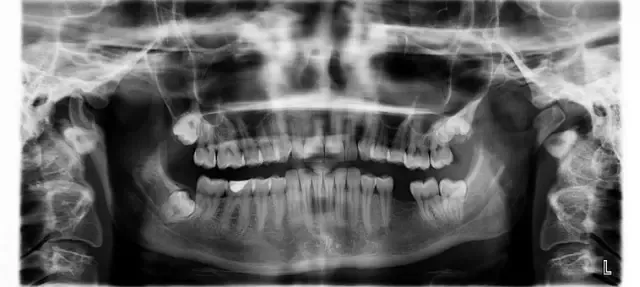

Naše delo je naše poslanstvo. Zavedamo se, kako pomembni so zdravi zobje za zdravje in samozavest posameznika, zato uporabljamo le najboljše materiale, aparate in pripomočke, kar lahko potrdi že veliko naših zadovoljnih strank in odličnih referenc. Dober privat zobozdravnik v Mariboru je sedaj na voljo tudi vam! Zavedamo se, da je strah pred obiskom zobozdravnika zelo pogost pojav, zato smo pri delu vedno nežni, razumevajoči in pristopamo brez kakršnegakoli obsojanja. Težave z zobmi se lahko pojavijo pri komurkoli - mi smo tukaj, da naredimo vse, kar lahko, da jih odpravimo.

Svoje znanje in izkušnje nenehno dopolnjujemo, sledimo novostim v zobozdravstvu tako doma kot po svetu in jih kot dober privat zobozdravnik v Mariboru uspešno vpeljujemo v svoje delo. Smo zanesljivi, odgovorni, prisluhnemo vašim željam in vam svetujemo glede na vaše stanje.

Ker smo dober privat zobozdravnik, Maribor že zelo dobro pozna naš pristop k delu in storitve, ki med drugim obsegajo: